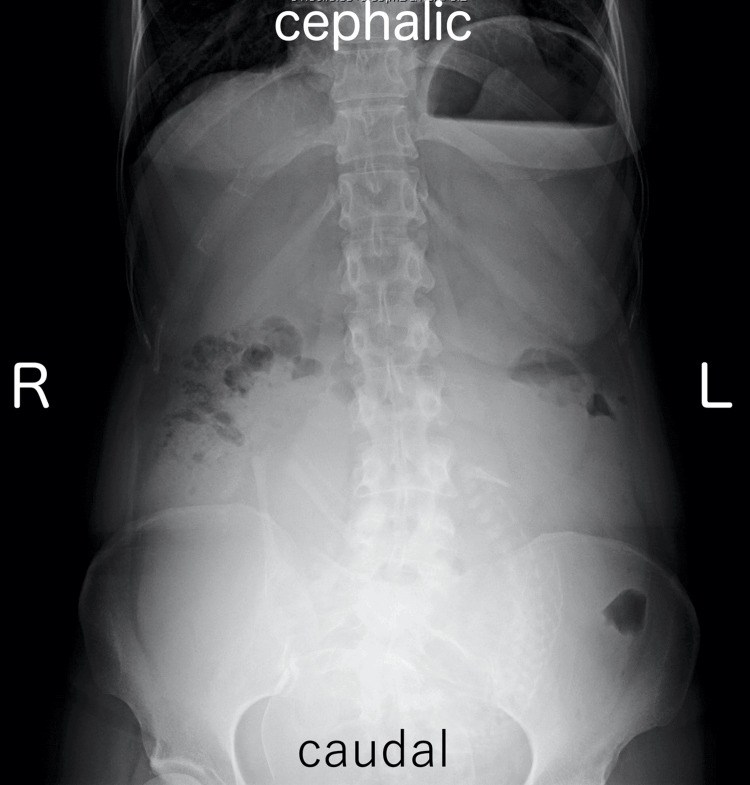

A 35-year-old woman, G1P0, presented with a medical history of CBD. At the age of two, she underwent hepaticojejunostomy with Roux-en-Y reconstruction after resection of the dilated extrahepatic bile duct. She obtained a spontaneous pregnancy and received prenatal care in our hospital from the beginning of the pregnancy. At 35 weeks and one day of gestation, she visited our emergency department due to epigastric pain and recurrent non-bilious vomiting. Her bowel movement was regular and showed normal brown stool. Vital signs were as follows: body temperature 35.8°C, blood pressure 108/76 mmHg, and pulse rate 83 beats per minute. Physical examination revealed spontaneous pain and mild tenderness in the epigastric region, while the abdomen was soft without signs of muscular defense or rebound tenderness. Obstetric examination showed a closed cervix with a cervical length of 30 mm on vaginal ultrasonography. Fetal heart rate monitoring indicated a reassuring fetal status. Blood tests showed a white blood cell count of 11,700/μL, C-reactive protein of 0.08 mg/dL (indicating an absent inflammatory response), and normal liver function with aspartate aminotransferase (AST) 28 IU/L, alanine aminotransferase (ALT) 23 IU/L, and total bilirubin 1.5 mg/dL. Abdominal ultrasonography revealed mild fluid retention in the Roux-en-Y limb at the porta hepatis (Figure 1). An abdominal X-ray, performed to rule out severe intestinal obstruction, showed displacement of the entire intestine due to the pregnant uterus, with partial colonic gas but no obvious signs of niveau formation or distal small bowel gas (Figure 2). Based on these findings, gastroesophageal reflux caused by compression from an enlarged uterus was suspected, and the patient was admitted to our hospital. Because there were limited signs suggesting intestinal obstruction, computed tomography was not performed to avoid unnecessary radiation exposure to the fetus.